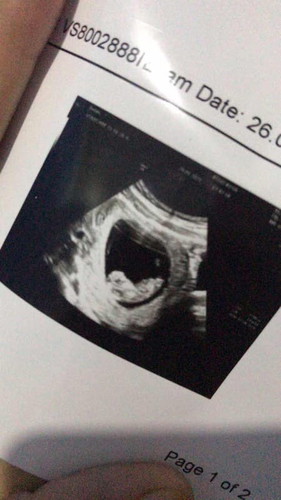

Assalamualaikum bunda saya pengen cerita tentang kehamilan saya , sebelumnya saya minta keikhlasan doa kalian untuk anak saya semoga anak saya diberi panjang umur dan dilancarkan persalinan saya nanti. ini anak pertama saya , dan kehamilan saya sekarang sudah 7bulan , saya baru usg 2kali , pertama saya usg pas awal awal hamil , dan usg yang ke dua baru beberapa hari yang lalu pas awal masuk 7bulan ini , pas saya kemarin usg di klinik yang 2d , kata dokter nya anak saya ada kelainan di dinding perut nya yang dimana kondisi usus anak saya berada diluar bukan di dalam perut , tapi dokternya tidak bisa memastikan itu benar atau tidak atau memang itu hanya ari ari , akhirnya saya disuruh minta rujukan di puskesmas dan saya disuruh usg di spesialis kandungan (RS hermina) pas saya kesana , yang nanganin saya dokter itu lagi yang di klinik , saya di usg lagi yang 2d dan jawaban dokternya tidak berubah , masih sama jawaban nya yang dimana anak saya mengalami kelainan gastroschisis , dan saya harus lahir secara sc dan nanti anak saya setelah lahir mau langsung di operasi 😭 denger perkataan begitu batin saya merasa sangat terpukul bgt 😭😭 mungkin disini ada yang pernah mengalami hal sama kaya sama saya ? 😭 #seputarkehamilanawal #ingintahu #jangandibully #pleasehelp